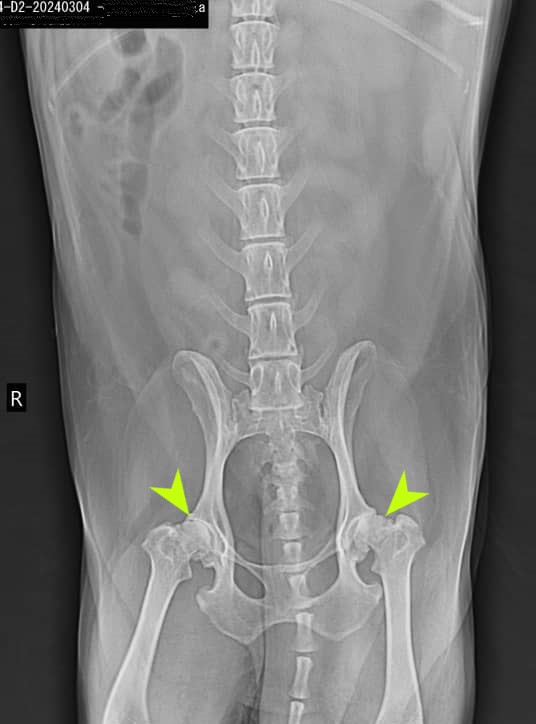

Pelvis and Proximal Hind Limbs:

– Radiographic signs of joint disease evident in both hip and knee joints.

– No other abnormalities identified.

Pelvis and Proximal Hind Limbs: Sever Osteoarthritis of the right and left Hip Knee Joints.